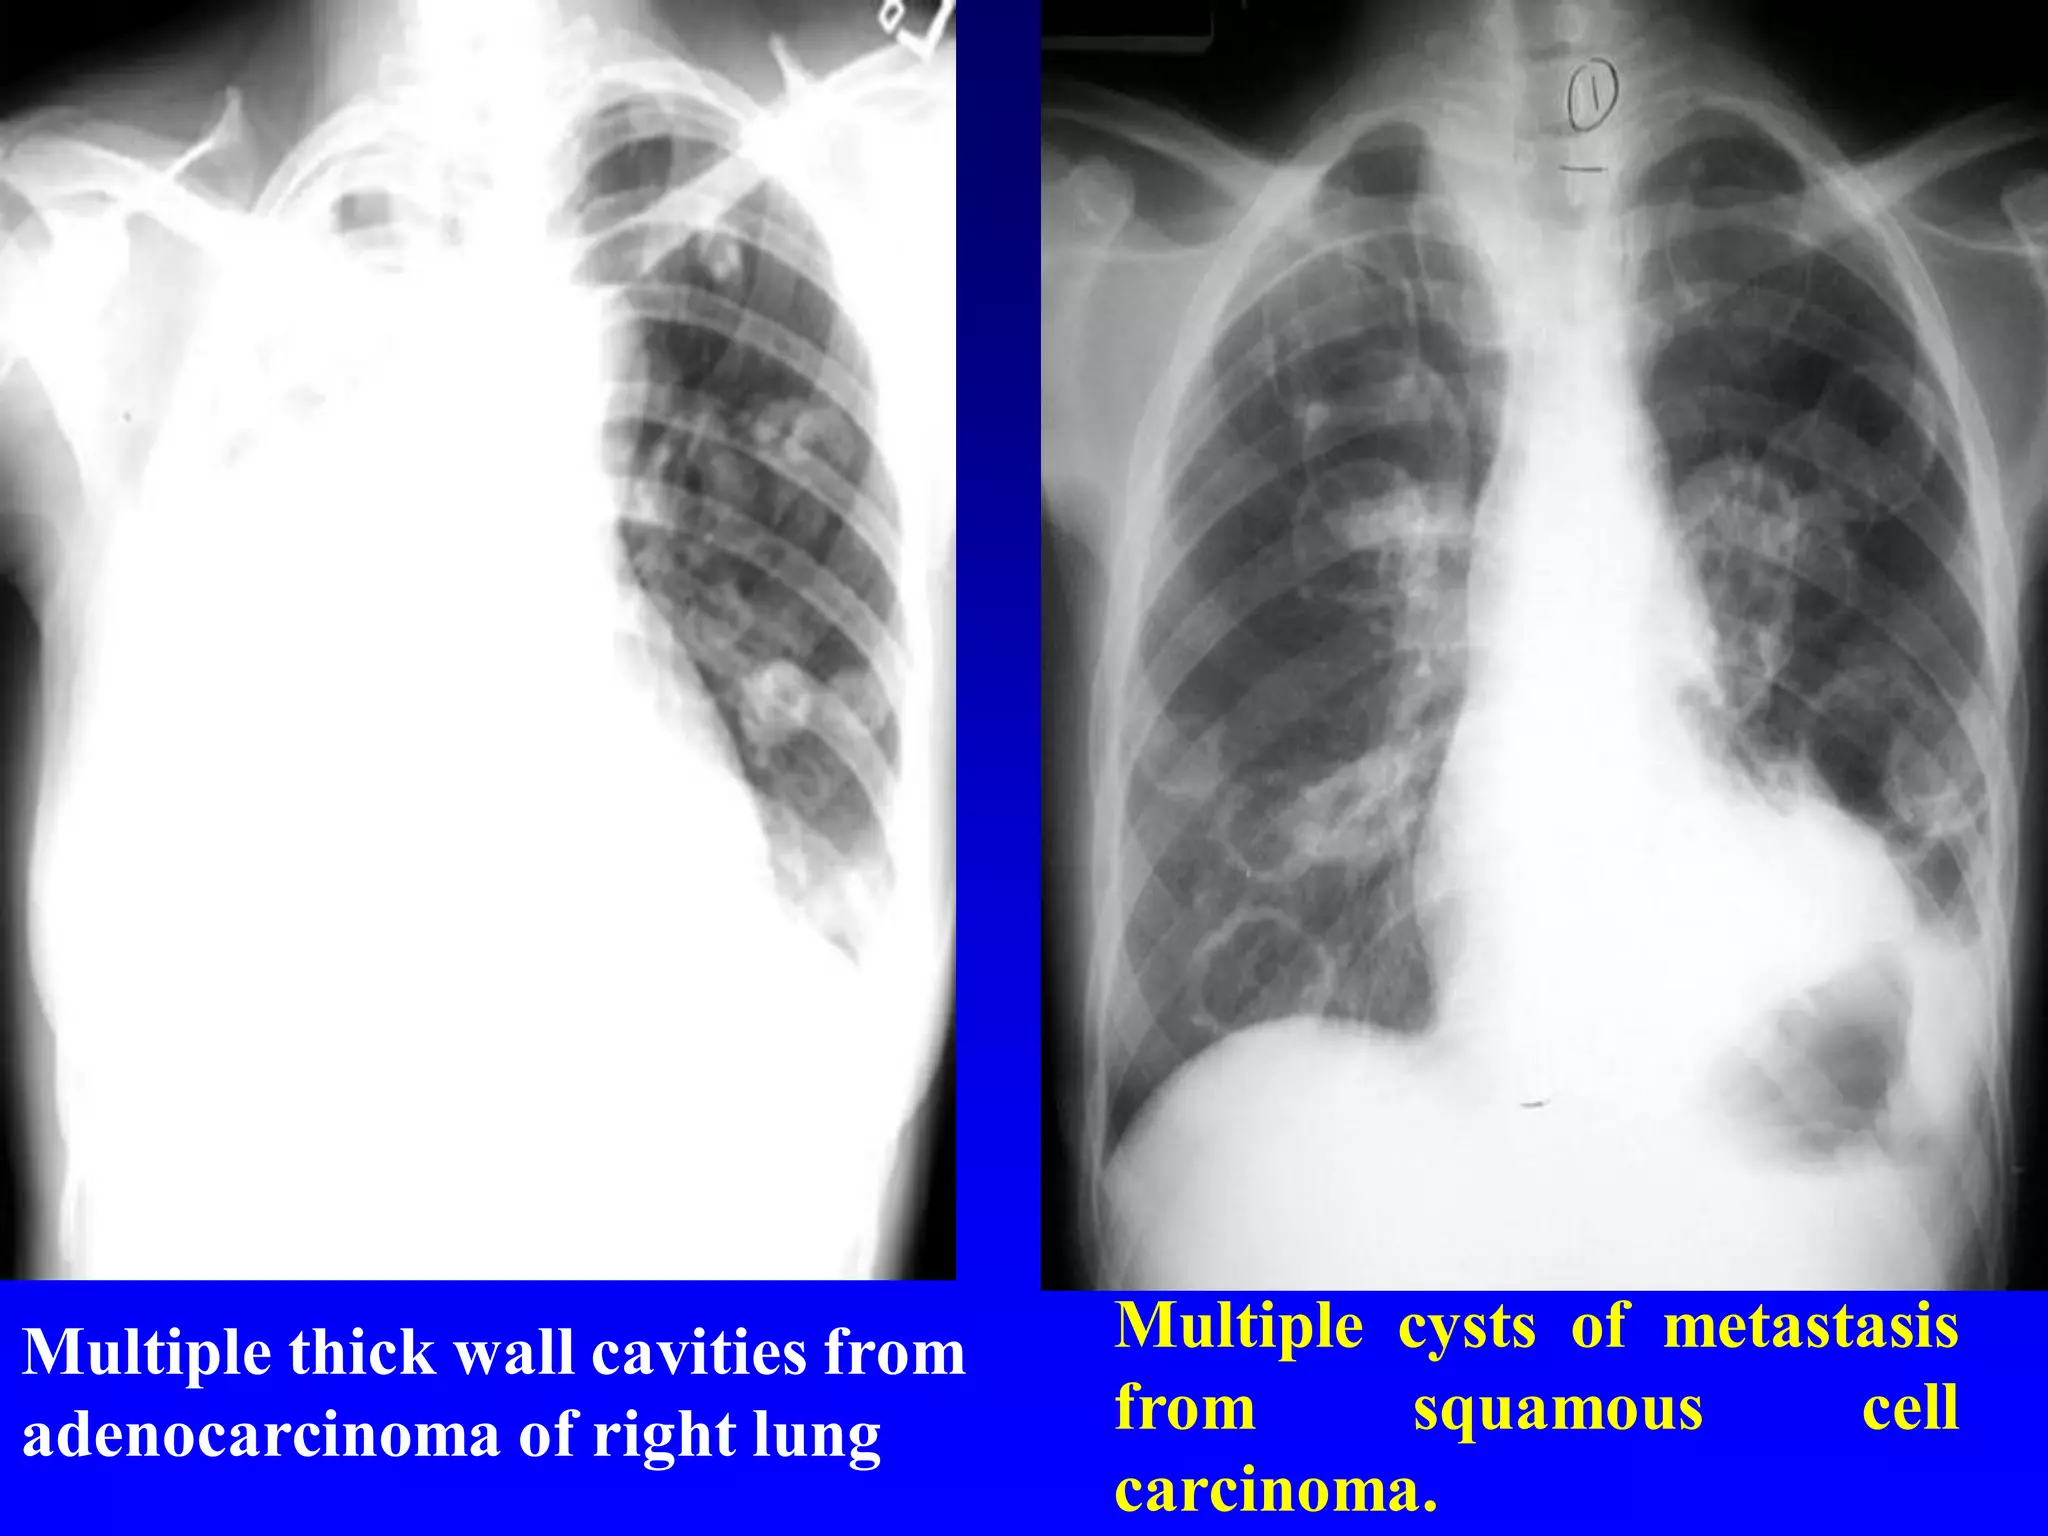

Multiple thick wall cavities from

adenocarcinoma of right lung

Multiple cysts of metastasis

from

squamous

cell

carcinoma.